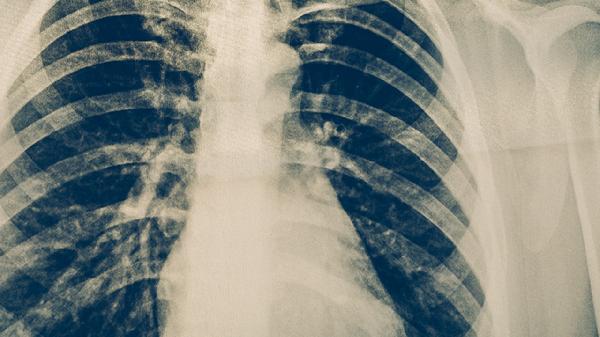

治疗期间需每月复查痰涂片、胸部X线或CT,评估治疗效果。每1-2个月监测肝功能、血常规等指标,及时发现药物不良反应。即使症状消失也需完成全程治疗,疗程结束后仍需随访1-2年。出现咳嗽加重、咯血等症状需立即复诊。